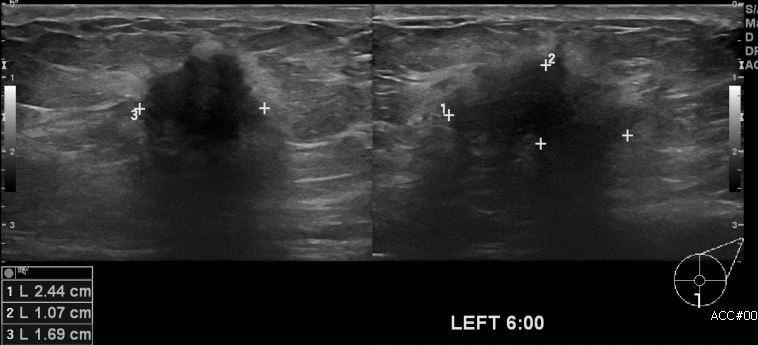

건강검진상 이상 소견으로 내원하신 60대 여성 분으로 좌측 6시 방향의 의심스러운 혹

조직검사 시행하여 좌측 침윤성 유관암 진단 되었습니다.